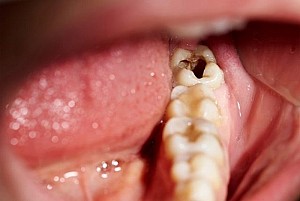

Đây là biến chứng thường gặp nhất vì sự tích tụ thức ăn và những vi khuẩn răng miệng tại vị trí răng khôn mọc lên gây viêm nhiễm tại chỗ – ở quanh vùng răng mọc. Người mọc răng thường thấy đau nhói, hôi miệng, sưng phù ở vùng lợi mọc răng khôn khiến cho việc há miệng khó khăn, thâm chí còn có thể chảy mủ ở vùng lợi bị viêm.

Tình trạng nhiễm trùng, viêm nhiễm này có thể bị tái phát lại nhiều lần, và những lần tái phát sau sẽ càng nặng nề và thời gian tái phát sẽ càng dày đặc hơn. Trong một số trường hợp nếu như người bệnh không được điều trị kịp thời thì tình trạng nhiễm trùng, viêm nhiễm sẽ ngày càng lan rộng ra, ảnh hưởng tới cả những chiếc răng khác, một số vùng khác của răng – hàm – mặt như là: cổ, mang tai, viêm xương, viêm màng tim, thậm chí là nhiễm trùng máu làm nguy hiểm đến tính mạng con người.

Răng số 8 mọc lệch thường làm hỏng răng bên cạnh là răng số 7. Tình trạng mọc lệch hình thành nên khe hở giữa răng khôn và răng số 7 dễ làm kẹt lại thức ăn, khiến khó vệ sinh, lâu ngày chắc chắn gây ra sâu răng. Khi răng khôn mọc lệch làm ép vào răng bên cạnh làm tiêu biến mất một phần thân và chân răng này.

Quá trình tổn thương có thể diễn ra trong âm thầm kéo dài trong nhiều năm, và cho đến khi bạn phát hiện ra thì tổn thương đã lan rộng gây biến chứng nặng. Khi đi đến phòng khám kiểm tra thì đôi khi răng số 7 đã bị hỏng, hư hại nặng không thể giữ lại được.